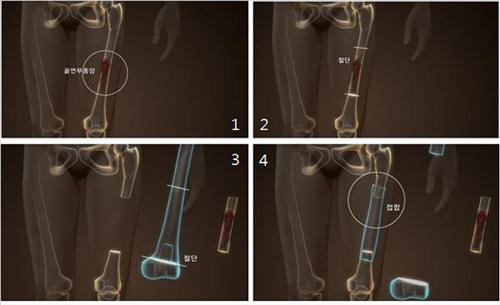

<±âÁ¸ ¹æ½Ä µ¿Á¾°ñ À̽Ĺý>

<Áßø ¹æ½Ä µ¿Á¾°ñ À̽Ĺý>